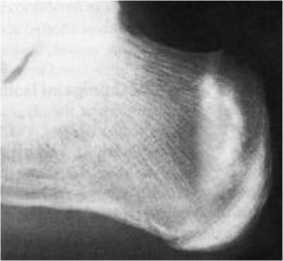

Рисунок 2 - Молодой человек 22 лет. Занимается футболом. Зона перестройки в пяточной кости в виде широкой полосы уплотнения костной ткани.